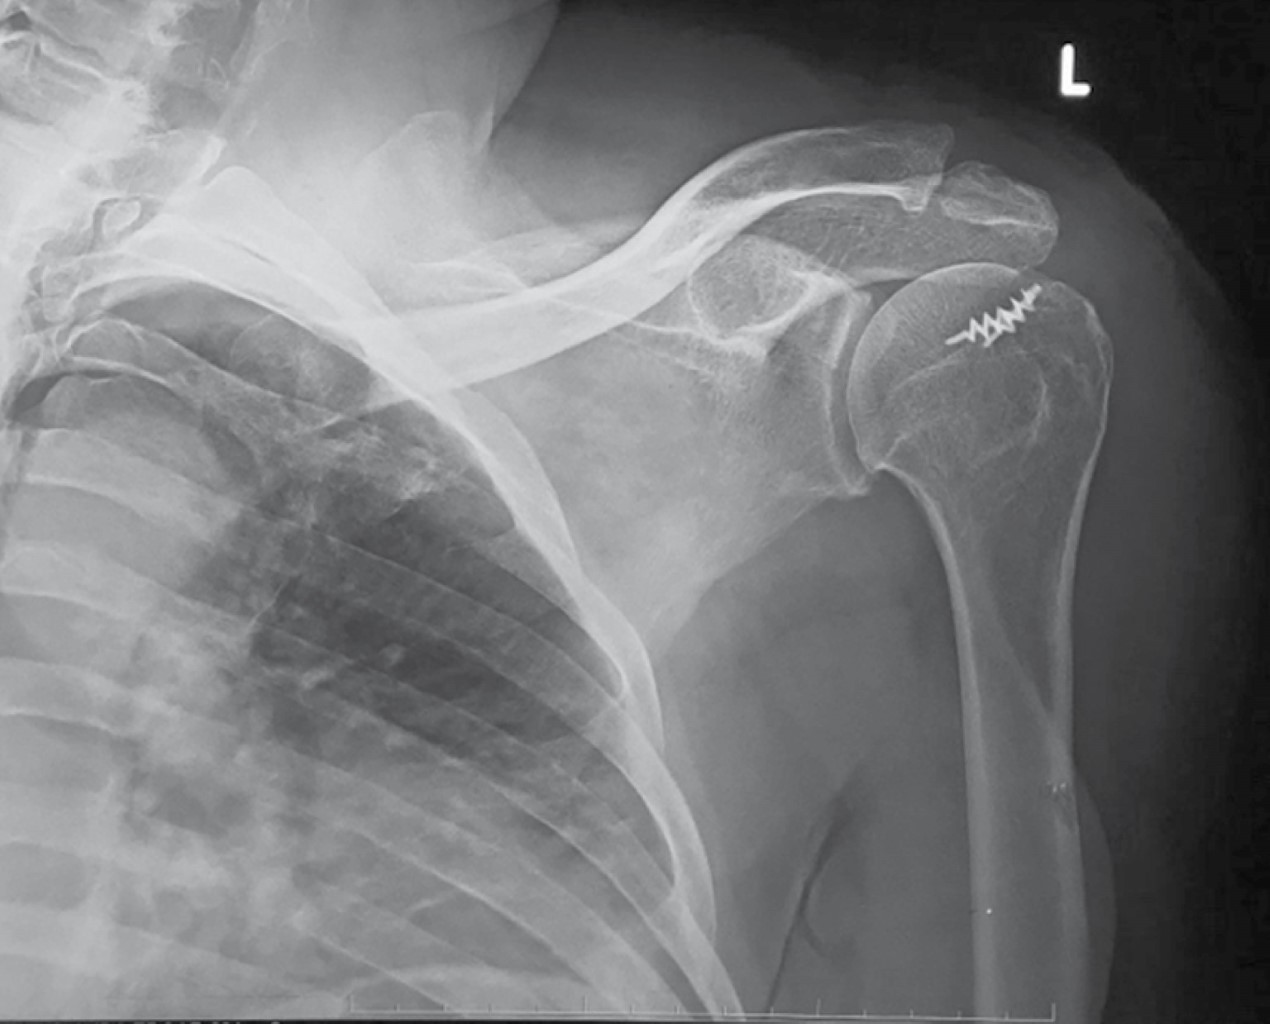

From www.medigraphic.com

Massive rotator cuff injury arthroscopic treatment with upper capsular reconstruction Rotator Cuff Capsular Pattern rotator cuff (rc) pathologies. Perhaps that's why the capsular patterns may be different. according to dutton, capsular patterns are based on clinical findings rather than research; The primary way to distinguish rc pathologies from frozen shoulder is to examine the specific. adhesive capsulitis (also known as frozen shoulder) is a condition of the shoulder characterized by functional. Rotator Cuff Capsular Pattern.

Massive rotator cuff injury arthroscopic treatment with upper capsular reconstruction Rotator Cuff Capsular Pattern rotator cuff (rc) pathologies. frozen shoulder can develop after a shoulder has been immobilized (held in one position without moving) for a period of time due to surgery, a fracture, or. according to dutton, capsular patterns are based on clinical findings rather than research; Perhaps that's why the capsular patterns may be different. examples include a. Rotator Cuff Capsular Pattern.

Massive rotator cuff injury arthroscopic treatment with upper capsular reconstruction Rotator Cuff Capsular Pattern rotator cuff (rc) pathologies. examples include a rotator cuff tear and fractures of your shoulder blade, collarbone or upper arm. The primary way to distinguish rc pathologies from frozen shoulder is to examine the specific. according to dutton, capsular patterns are based on clinical findings rather than research; adhesive capsulitis (also known as frozen shoulder) is. Rotator Cuff Capsular Pattern.

Massive rotator cuff injury arthroscopic treatment with upper capsular reconstruction Rotator Cuff Capsular Pattern stage 1, the preadhesive stage, demonstrates mild erythematous synovitis. The primary way to distinguish rc pathologies from frozen shoulder is to examine the specific. frozen shoulder can develop after a shoulder has been immobilized (held in one position without moving) for a period of time due to surgery, a fracture, or. examples include a rotator cuff tear. Rotator Cuff Capsular Pattern.